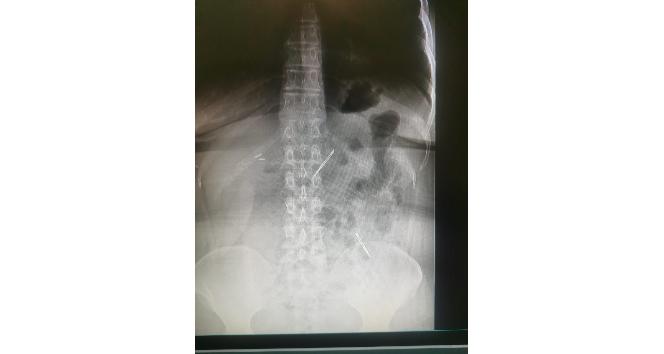

Sağlık Bilimleri Üniversitesi Ankara Atatürk Sanatoryum Eğitim ve Araştırma Hastanesi’ne mide ve karın bölgesinde aşırı ağrı şikayeti ile müracaat eden 46 yaşındaki D.E.’nin yapılan tahlil, tetkik ve çeşitli görüntülemelerden sonra bağırsak kısmında 2 adet neşter olduğu tespit edildi. Genel cerrahi kliniği tarafından zorlu bir ameliyat sonrasında neşterler kadının vücudundan çıkarıldı. 46 yaşındaki D.E. neşterleri nasıl yuttuğunu bilmediğini tahminen ekmek ile birlikte yutabilmiş olabileceğini ifade etti. Ameliyatı gerçekleştiren Sağlık Bilimleri Üniversitesi Ankara Atatürk Sanatoryum Eğitim ve Araştırma Hastanesi Genel Cerrahi Kliniği Eğitim ve İdari sorumlusu Prof. Dr. Hakan Buluş ise hastanın yoğun şikayetleri üzerine çektikleri röntgen sonrasında 2 adet neşteri görünce şaşkına uğradıklarını söyledi.

Hastanın şikayetlerinin artması üzerine gerçekleştirilen tetkiklerde 46 yaşındaki kadının karın bölgesinde 2 adet yabancı cisim olduğunu tespit ettiklerini, detaylı inceleme sonucunda bu cisimlerin neşter olduğunu fark ettiklerini belirten Prof. Dr. Buluş, “Yaklaşık 10 gün önce kliniğimize karın ağrısı ve bulantı şikayetleri ile başvurdu. Bizim yaptığımız fiziki muayene ve tetkiklerinde hastanın direkt karın grafisinde 2 adet yabancı cisim olduğunu tespit ettik. Aslında yabancı cisim bizim güncel grafiğimizde sık karşılaştığımız bir durum değil, fakat nadir de olsa görebildiğimiz bir patoloji. Biz de bunun üzerine ayrıntılı değerlendirmeler ve tetkikler yaptık. Sonrasında 2 adet yabancı cismin bistüri (neşter) ile uyumlu olduğunu gördük. Bunun üzerine hastanın şikayetlerinin de artması üzerine, ameliyat kararı verdik. Yaptığımız ameliyatta ince bağırsağın yaklaşık 180’inci santimetresinde bu yabancı cisimlerin olduğunu tespit ettik. Bunun üzerine ameliyatla bunları çıkarttık. Hastamızın sağlık durumu şuan gayet iyi. Ameliyattan sonraki üçüncü günü. Şuan bir problemi yok, inşallah birkaç gün içerisinde şifa ile taburcu etmeyi düşünüyoruz” şeklinde konuştu.

Çıkardıkları cismin, neşterin normalde ameliyatlarda kullanılan bir malzeme olduğunu söyleyen Prof. Dr. Buluş, “Çıkardığımız yabancı cisimler bizim ameliyatlarda sıkça kullandığımız 11 numara dediğimiz bir bistüri tipi. Ebatları da yaklaşık 4 santime yarım santim ebatlarında. Ucunun sivri olması nedeniyle ince bağırsak mukozasına saplanarak enflamasyon ve bir karın ağrısı yapması, sonrasında da ağrı şikayetlerinin artmasına neden olmasından dolayı ameliyat kararı verdik” diye konuştu.